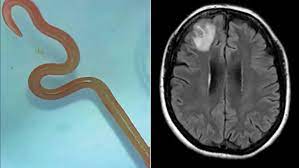

Los primeros síntomas del Ophidascaris robertsi aparecieron en 2021 cuando la afectada de 64 años tuvo que ingresar en el hospital por primera vez tras semanas de dolor en el abdomen y diarrea además de tos seca y fiebre. El neurocirujano que la atendió en el momento -y que posteriormente le extraería el parásito-, el Dr. Hari Priya Bandi, acudió al Dr. Sanjaya Senanayak para encontrar en él la ayuda necesaria como para identificar qué le ocurría a la mujer, pero no sería hasta 2022 cuando la aparición de nuevos síntomas como olvido y depresión desvelaron ciertas anomalías que debían requerir cirugía después de una resonancia magnética.

La primera respuesta ante este hallazgo fue una reunión entre todo el equipo médico para tratar de averiguar la clase de parásito -en este caso de lombriz- y qué tratamiento debería necesitar la paciente con el objeto de no perjudicar en ningún momento cualquier tipo de órganos.

Una vez dicha búsqueda no determinó nada, el siguiente paso fue el envío de este gusano a un laboratorio científico de CSIRO, con experiencia en parásitos. Ahí fue cuando se le puso nombre y apellidos: Ophidascaris robertsi.

Este gusano se encuentra, por lo general, en las pitones dando la casualidad que la paciente afectada residía en la zona de un lago donde habitaban las denominadas “pitones de alfombra”. Si bien no tenía contacto directo con ellas, la recolección de pastos nativos que posteriormente serían cocinados sería causa suficiente para la transmisión de esos parásitos. Una de las hipótesis barajadas por los expertos ha explicado que podría ser que la pitón los depusiera en la hierba a través de sus heces.

Al tratarse del primer caso de parásitos en humanos era importante llevar especial cautela al ser tratada -también por otras larvas-. El porqué residiría en la posible inflamación de los órganos cuando, al administrar el medicamento, las larvas mueren, lo que acarrearía determinadas consecuencias en órganos esenciales como el cerebro. “La paciente se está recuperando bien y todavía está siendo monitoreada regularmente”, dijo Senanayake.